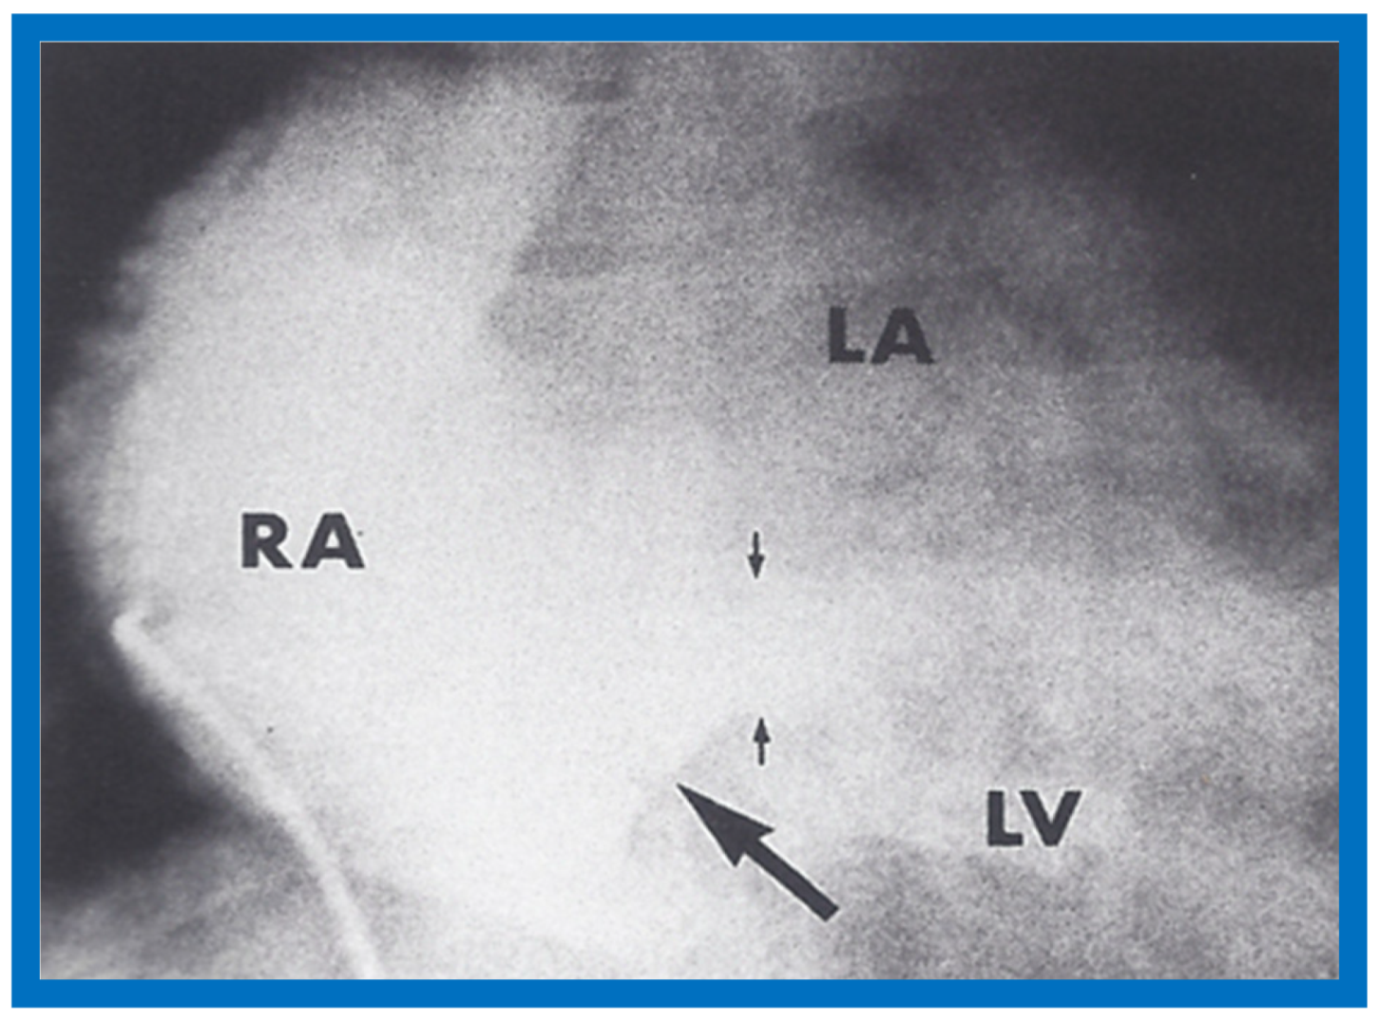

The author reported on the clinical, radiographic, ECG, echocardiographic and hemodynamic features of a rare case of common atrioventricular canal (currently called atrioventricular septal defect) mimicking tricuspid atresia in an eight-year-old child [15]. The clinical, radiographic and ECG characteristics were similar to those of classic tricuspid atresia. Hemodynamic data secured at cardiac catheterization were also similar to those seen with tricuspid atresia. A two-dimensional echocardiogram demonstrated an ostium primum atrial septal defect with a common atrioventricular valve and a small RV (Figure 50a,b); the entry into the RV appeared to be occluded by a leaflet of the common atrioventricular valve. Left ventricular cineangiogram in postero-anterior view demonstrated “gooseneck” deformity, similar to that seen in atrioventricular canal defects [15]. However, right atrial angiography resulted in direct emptying of the contrast material into the left ventricle via an ostium primum atrial septal defect (Figure 51). The floor of the right atrium seemed to be formed by a leaflet of the common atrioventricular valve (Figure 51). Thus, the two-dimensional echocardiographic and right atrial cineangiographic features appeared to be distinctive, and could be utilized to distinguish this anomaly from other varieties of tricuspid atresia.

Figure 51.

Selected right atrial (RA) angiographic frame in postero-anterior view demonstrating that the floor of the right atrium is formed by one of the leaflets of the atrioventricular valve; this is marked by a large arrow. The contrast material exited the RA via an ostium primum atrial septal defect shown by small arrows with subsequent opacification of the left ventricle (LV). C, catheter; LA, left atrium. Reproduced from Rao P.S. [15].